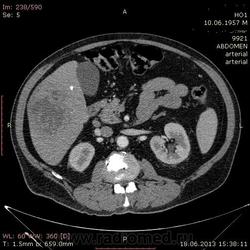

- https://radiomed.ru/sites/default/files/styles/case_slider_image/public/user/17529/img-0005-00001_3.jpg?itok=_YnH55Nh

На абсцесс похоже

+1. Контраст вводили?

На мой взгляд, абсцесс.

Тоже за абсцесс.

Cпасибо , коллеги.Сегодня больного прооперировали диагноз абсцесс правой доли печени.Оказывается больной когда - то получил тупую травму живота, об этом нам не говорил.....